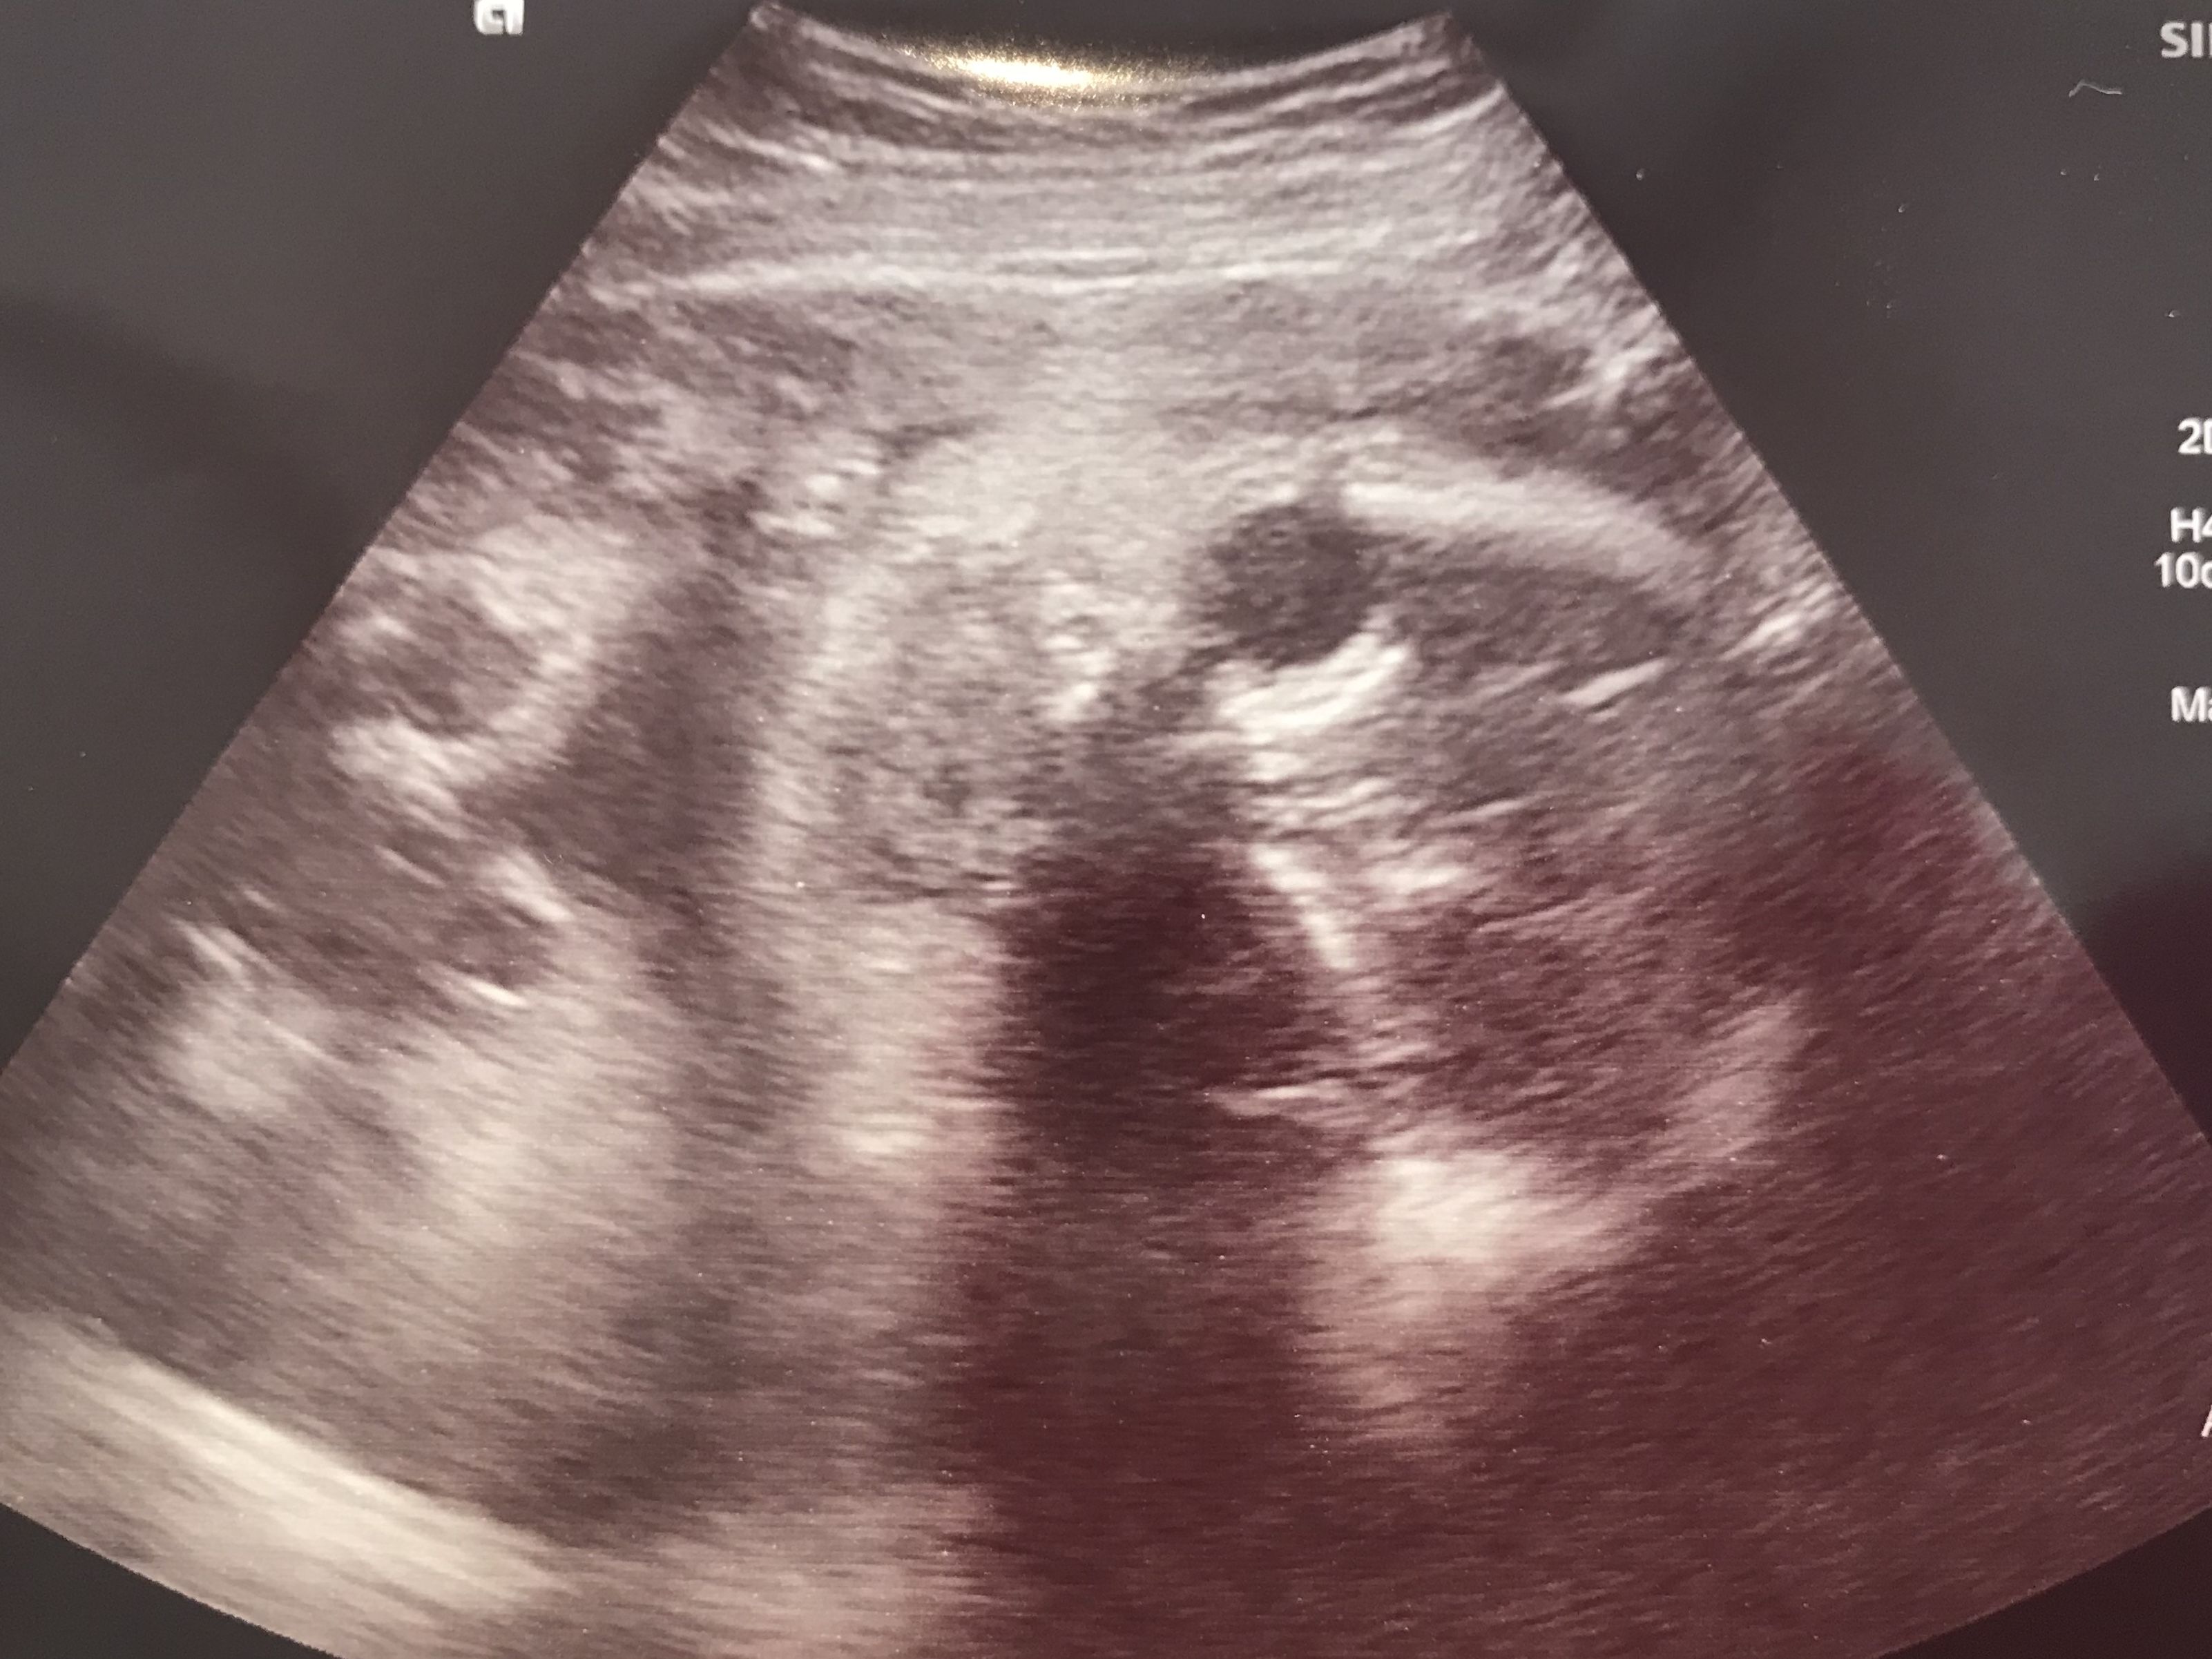

(助産師さんに「ここが目でここが口で〜」って説明されるけど、さっぱりよくわからなかったエコー写真)